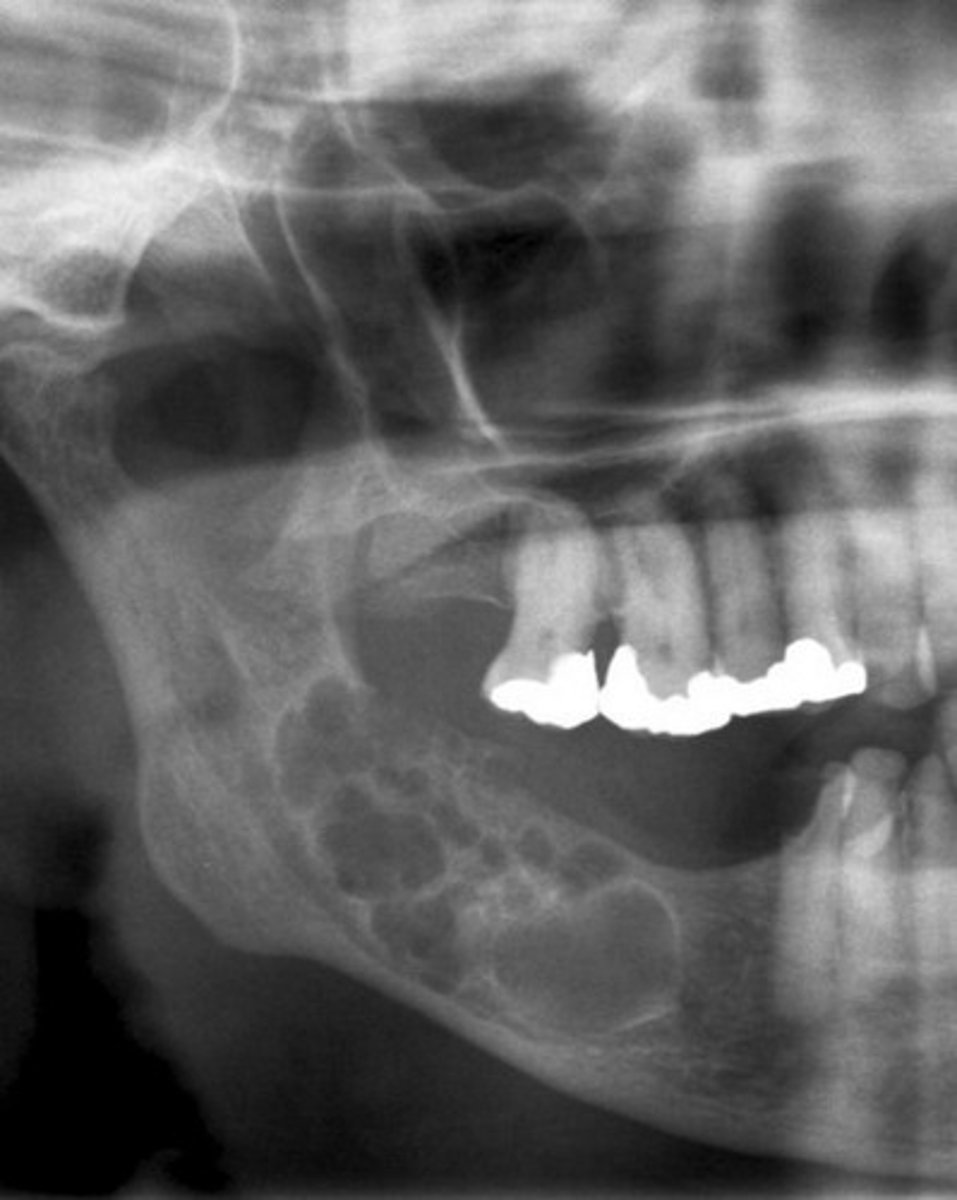

ameloblastoma radiographically theres 5

-at early stage uniocular

-multilocular radiolucency's (honeycomb, soap bubbles)

-cortical thinning of bone

-reabsorption of adjacent tooth roots

-Tooth displacement

ameloblastoma